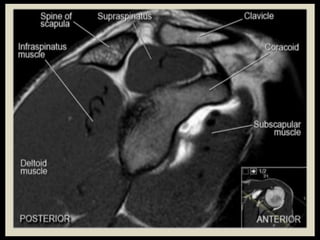

Shoulder

Joint.